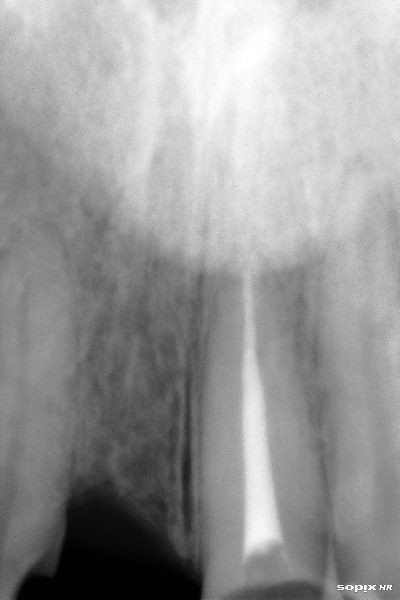

Radiografía inicial

Endodoncia terminada en incisivo central izquierdo